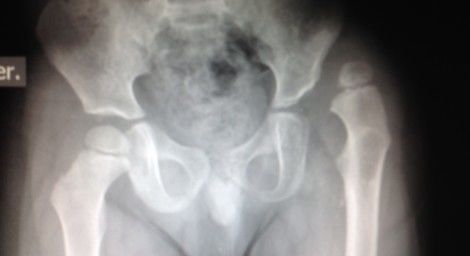

• displacia congenita de cadera

• Es una dislocación de la articulación de la cadera que está presente al nacer y es una afección que se encuentra en bebés o niños pequeños.